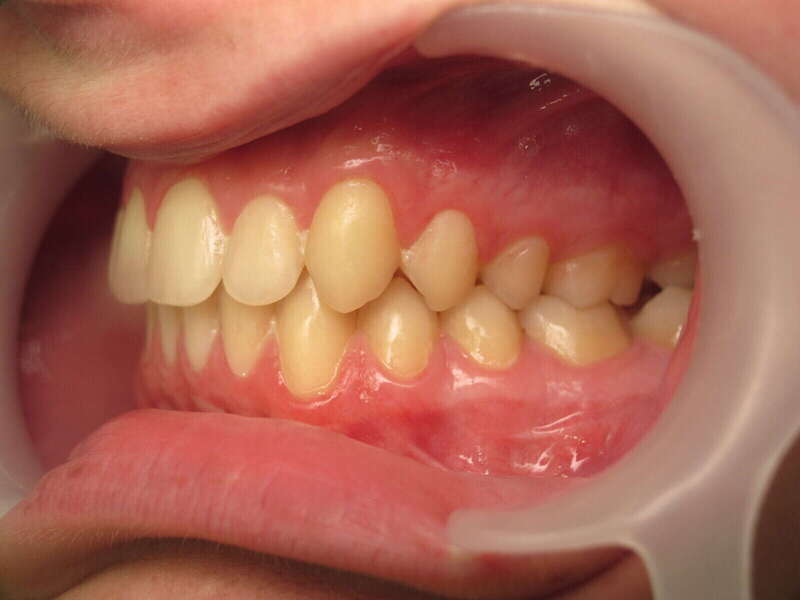

Cas n°9 traité par multi-attaches - adolescent

Ce cas d'adolescent illustre une stratégie de développement d'arcade réussie. Le patient présentait un encombrement massif et des inversions d'articulé rendant l'occlusion instable.

Le traitement a été réalisé avec des multibagues autoligaturantes, choisies pour leur capacité à générer des forces légères et continues, idéales pour l'expansion transversale. Cette approche a permis de corriger l'encombrement et les inversions d'articulé sans extractions dentaires, en remodelant simplement la forme des arcades.

Résultats clés :

• Transformation d'arcade : Passage d'une arcade étroite et encombrée à une arcade large et fonctionnelle.

• Occlusion optimale : Rétablissement d'un engrènement sain, protégeant les dents contre les usures anormales.

• Esthétique naturelle : Le sourire est élargi, harmonieux et parfaitement intégré au profil du patient.

C'est une démonstration de l'efficacité biologique de l'orthodontie moderne, qui privilégie la conservation dentaire et le respect des structures osseuses.

Avant le traitement

Pendant le traitement

Après le traitement